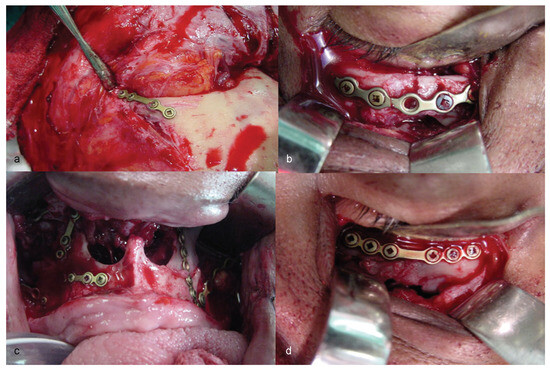

Thus, the possibility of CCF-type vascular complication was discussed with the neurosurgery team. Three-dimensional (3D) facial reconstruction was performed, using bone grafting and titanium (Ti) plates to obtain stable internal fixation of the facial skeleton (Figure 5). Treatment progressed well up to the 15th postoperative day (POD), when signs and symptoms of CCF began, and the patient had to be treated for it.

Figure 5.

(a–d) Stages of three-dimensional reconstruction of the face, using stable skeleton fixation by means of titanium plates and screws.